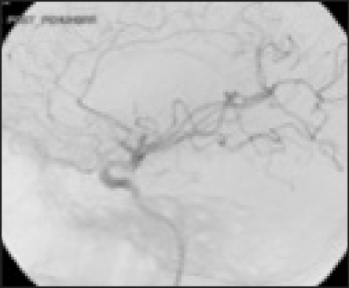

See Figures 1(i)-3(ii) for images of a successful endovascular therapy case.

Figure 1 (i): this and Figure 1(ii) show axial and coronal CT angiogram identifying proximal right MCA (M1) occlusion(click to enlarge)